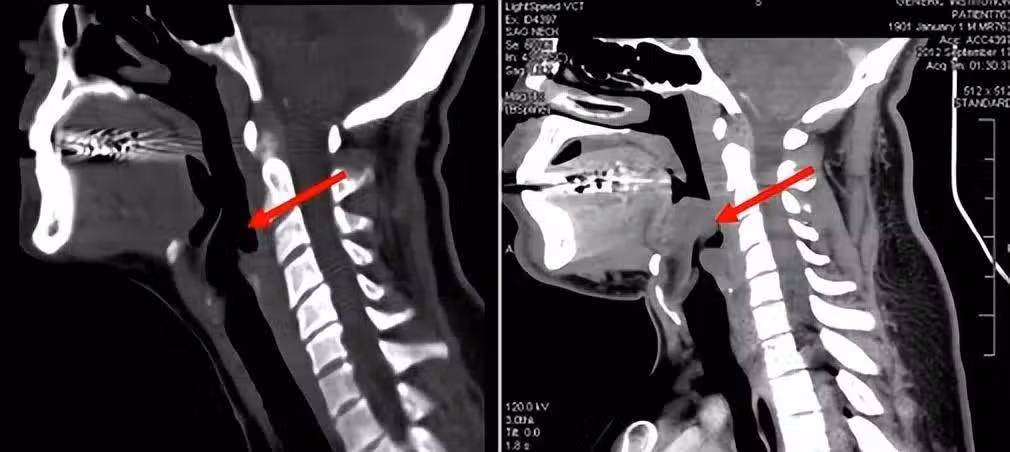

一般,急性會厭炎的病情進展十分迅速,一旦發病後沒有及時診療,可在極短時間內窒息,因此死亡率較高。

第一個是感染,比如年老體弱或有喉外傷的人,就很容易受到細菌或病毒感染。過敏體質的人在過敏後,也可能出現會厭炎。

其次是外部創傷,如果喉嚨受到外力創傷,或吸入高熱飲品以及有害氣體時,會厭也會受到損害。異物刺入也可能引發急性會厭炎。